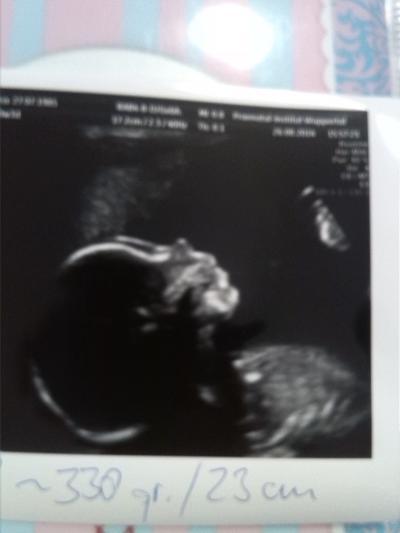

Hallo zusammen :) ich hatte heute das organscreening und es ist alles wie es sein soll... es wird ein junger :) was auch insgeheim mein Wunsch war! ABER: ich hab Wasser in der Plazenta oO der doc meinte zwar da der kurze zeitgerecht entwickelt ist ist das erst mal nichts schlimmes, trotzdem bin ich leicht verunsichert.. kennt das jemand und weiss was dazu ..? Aber erst mal ist die Hauptsache das alles soweit gut ist.. der Arzt war total begeistert von der Nase :D er sagte immer "was für ein stupsnäschen" und musste schmunzeln.. ich bin echt happy :)

Bild zu organscreening - Forum für Januar - Mamis

Süßes Bild vom Profil Freut mich, dass der Kleine so gut entwickelt ist und bis auf das Wasser alles normal ist. dass es so bleibt.... Lg Khadi